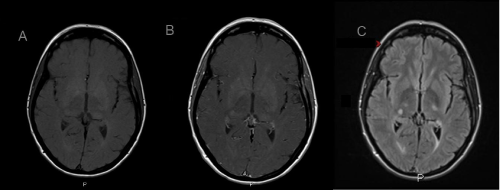

| Figure 2: (A) MRI axial brain T1 normal. (B) MRI axial brain T1 post contrast, shows a 7 mm contrast enhancing lesion within the posterior right lateral thalamus. (C) MRI T2 axial brain fluid-attenuated inversion recovery (FLAIR) shows a 7 mm hyperintensity within the posterior right lateral thalamus. |